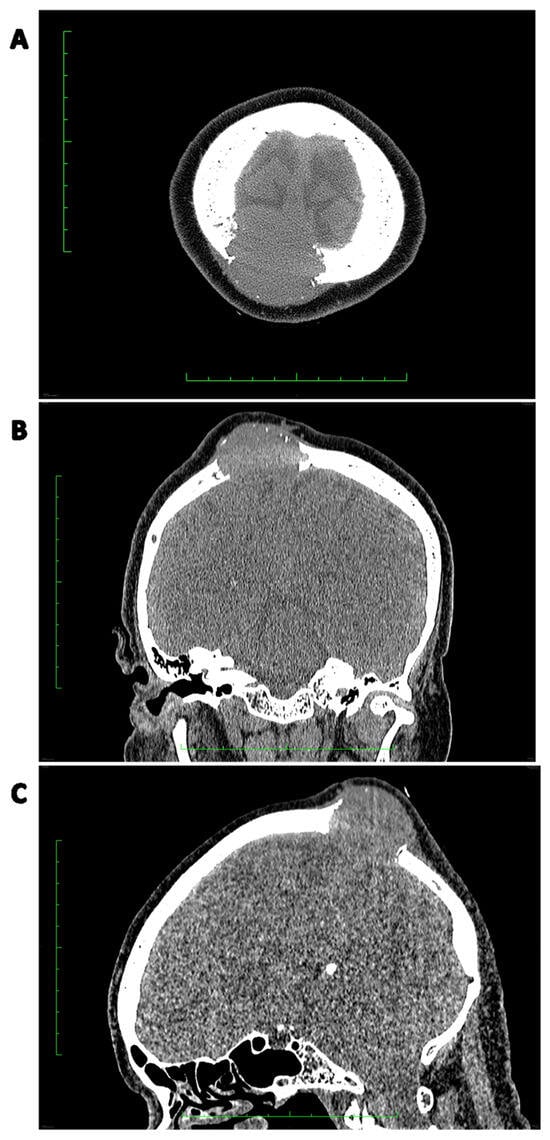

4. Diagnosis

5. Clinical and Radiological Differential Diagnosis